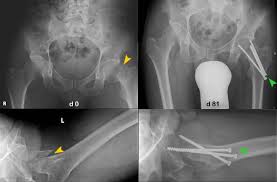

Bei den dabei verwendeten sogenannten Marknägeln handelt es sich meist um Implantate aus Titan oder Edelstahl. Die Diagnose Multiples Myelom in Deutschland fälschlicherweise oft mit dem solitären Plasmozytom gleichgesetzt löst Schock Angst und Ratlosigkeit aus. Es blieben subtrochantär große Löcher im Femur mit einer lateralen kortikalen Lücke von 12x12 mm und einer weiteren.

Immerhin wird das Bein bin zum Knochen geöffnet Gewebe und Muskeln durchtrennt und es verbleiben Löcher in den Knochen. Die Schraube im Schenkelhals ließ sich noch lösen die zwei Verriegelungsschrauben jedoch nicht - die Schraubenköpfe brachen ab die Gewinde wurden überbohrt und brachen wieder ab. Da die Drähte bei auch nur leichter Lockerung eine Gefahr für Strecksehen darstellen gibt es sehr gute Gründe die Kirschnerdrähte zu entfernen.

Es wurde schließlich alles Metall entfernt aber leider zu einem hohen Preis.